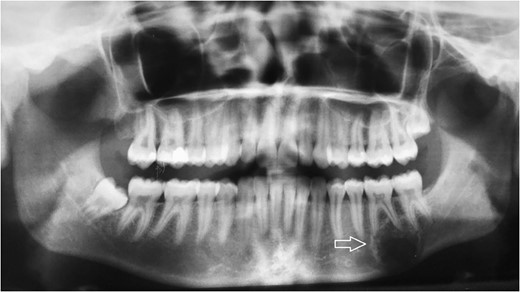

Radiologic diagnostics in two planes with panoramic X-ray. The panoramic radiograph showed a 2 × 1.8-cm radiolucent lesion of the left mandible. The lesion involved both apices of the first molar and the mesial apex of the second molar and extended to the caudal border of the mandibular bone.